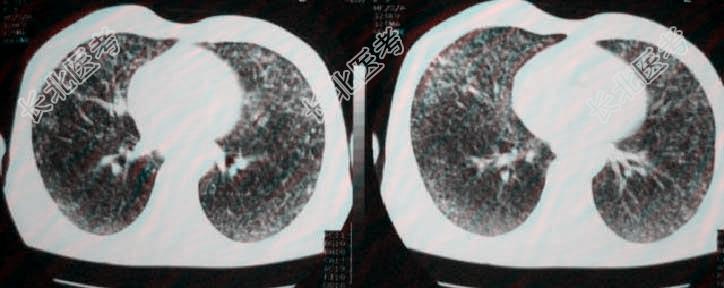

- 多项选择题10.提示:经给予左克.头孢吡肟.去甲万古霉素.氟康唑治疗4天, 仍持续高热,且病情加重出现呼吸衰竭。吸氧3.5L/分条件下, 血气:PH7.49, PaO₂46.8mmHg,PaCO₂7.4mmHg, HCO₃⁻20.4mmol/L,AaDO₂68.4mmHg。6月6日胸片及CT示双肺弥漫性结节状密度增高影, 内见细支气管充气征,纵膈内有肿大淋巴结。如下图。

此时首先考虑哪些诊断: A、血行播散型结核病